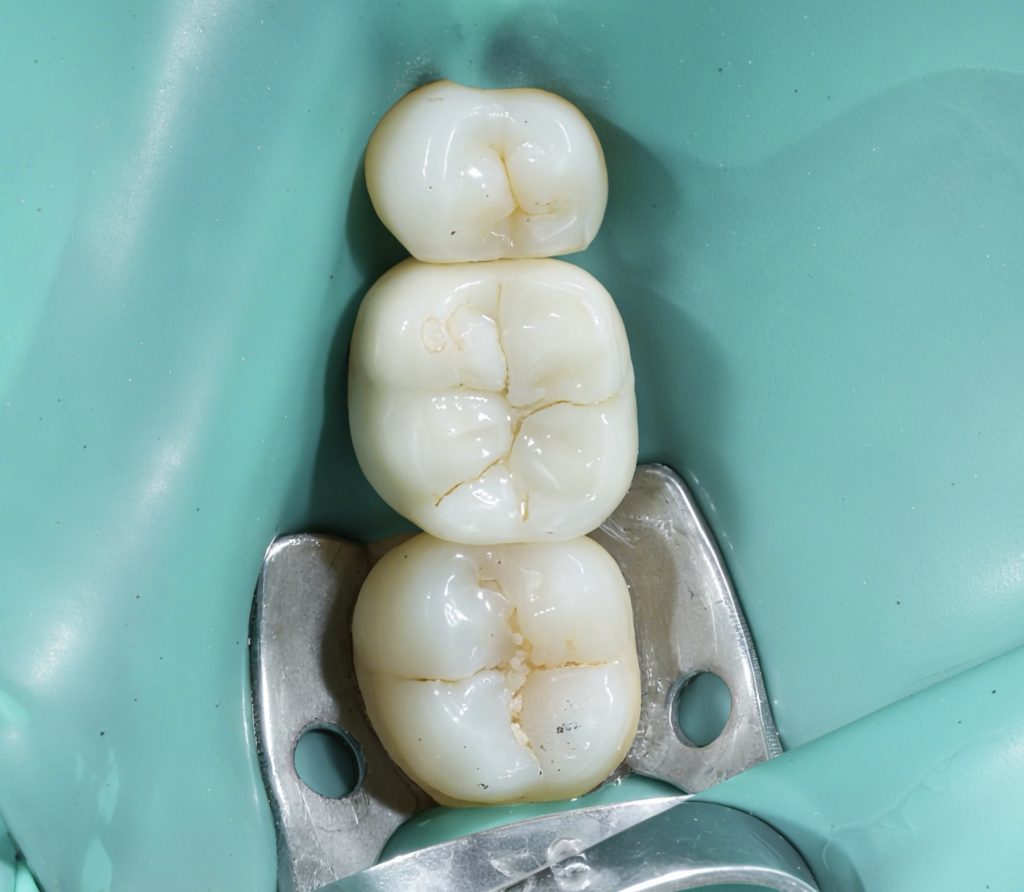

5️⃣ Occlusal Anatomy & Finishing

The enamel replacement was sculpted using Tokuyama Estelite Sigma Quick A2/A3 shades, carefully replicating fissure architecture and line angles under microscope-assisted magnification.

Final contouring and gloss were obtained with Dentsply Enhance Finishing System, PoGo, and Lucida Polishing Paste.

4️⃣ Immediate post-operative result under magnification